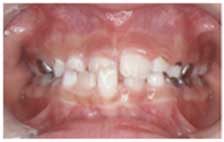

27. 交叉咬合の治療例

子供の時の交叉咬合は、比較的短期間で治療が可能です。どの歯をどの方向に動かすかを決定し、その動きにあった、一番望ましい装置で治療します。

この治療はリンガルアーチという装置で行っています。細い針金で動かした後、歯が後ろに戻らないように、止めています。